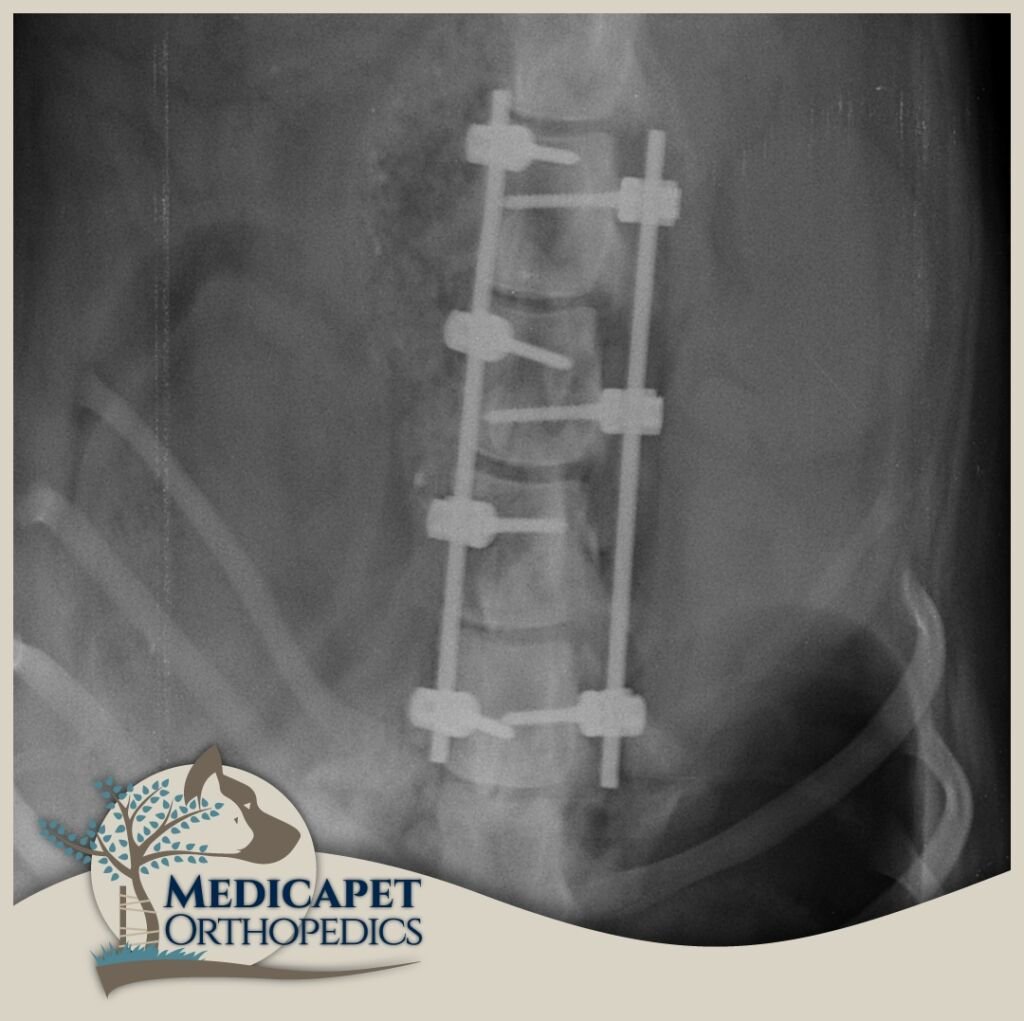

Kemik dokulara paralel seyreden ya da onların içinde bulunan sinir yapıları, kemik hasarlarıyla birlikte zarar görebilir. Yumuşak yapılı sinir dokuları en küçük travmaya karşı hassastır ve korunmaya ihtiyaç duyar. Beyin ve omurilik gibi organlar kafatası ve omurga tarafından korunur, bu nedenle kemik dokuların tedavi ve onarımı sinir dokusuna zarar vermeden yapılmalıdır. Ayrıca bazı sinir hastalıklarında da (örneğin tümörler) kemik dokuya müdahale gerekebilir. Bu yüzden nöroloji ve ortopedi yakından ilişkilidir.

Sinir sistemi; Merkezi Sinir Sistemi (beyin, beyincik, beyin sapı, omurilik) ve Periferik Sinir Sisteminden (gangliyonlar, sinirler, sinir uçları) oluşur. Kliniğe başvuran hastaların çoğunda trafik kazaları, düşme, saldırılar gibi nedenlerle omurga kırıkları, kafatası travmaları veya felç durumları görülmektedir. Bazı ırklarda genetik yatkınlık da omurga sorunlarına yol açabilir.

Nörolojik cerrahide operasyon kadar öncesi ve sonrası bakım da önemlidir. Operasyon sonrası ödem sinir dokularda bası oluşturabileceğinden dikkatli cerrahi, uygun ilaç tedavisi ve gerektiğinde fizik tedavi süreci titizlikle uygulanmalıdır. Sinir dokusu diğer dokulara göre çok daha yavaş iyileşir; küçük bir kesik deride kısa sürede düzelirken omurilikte kalıcı felce yol açabilir.